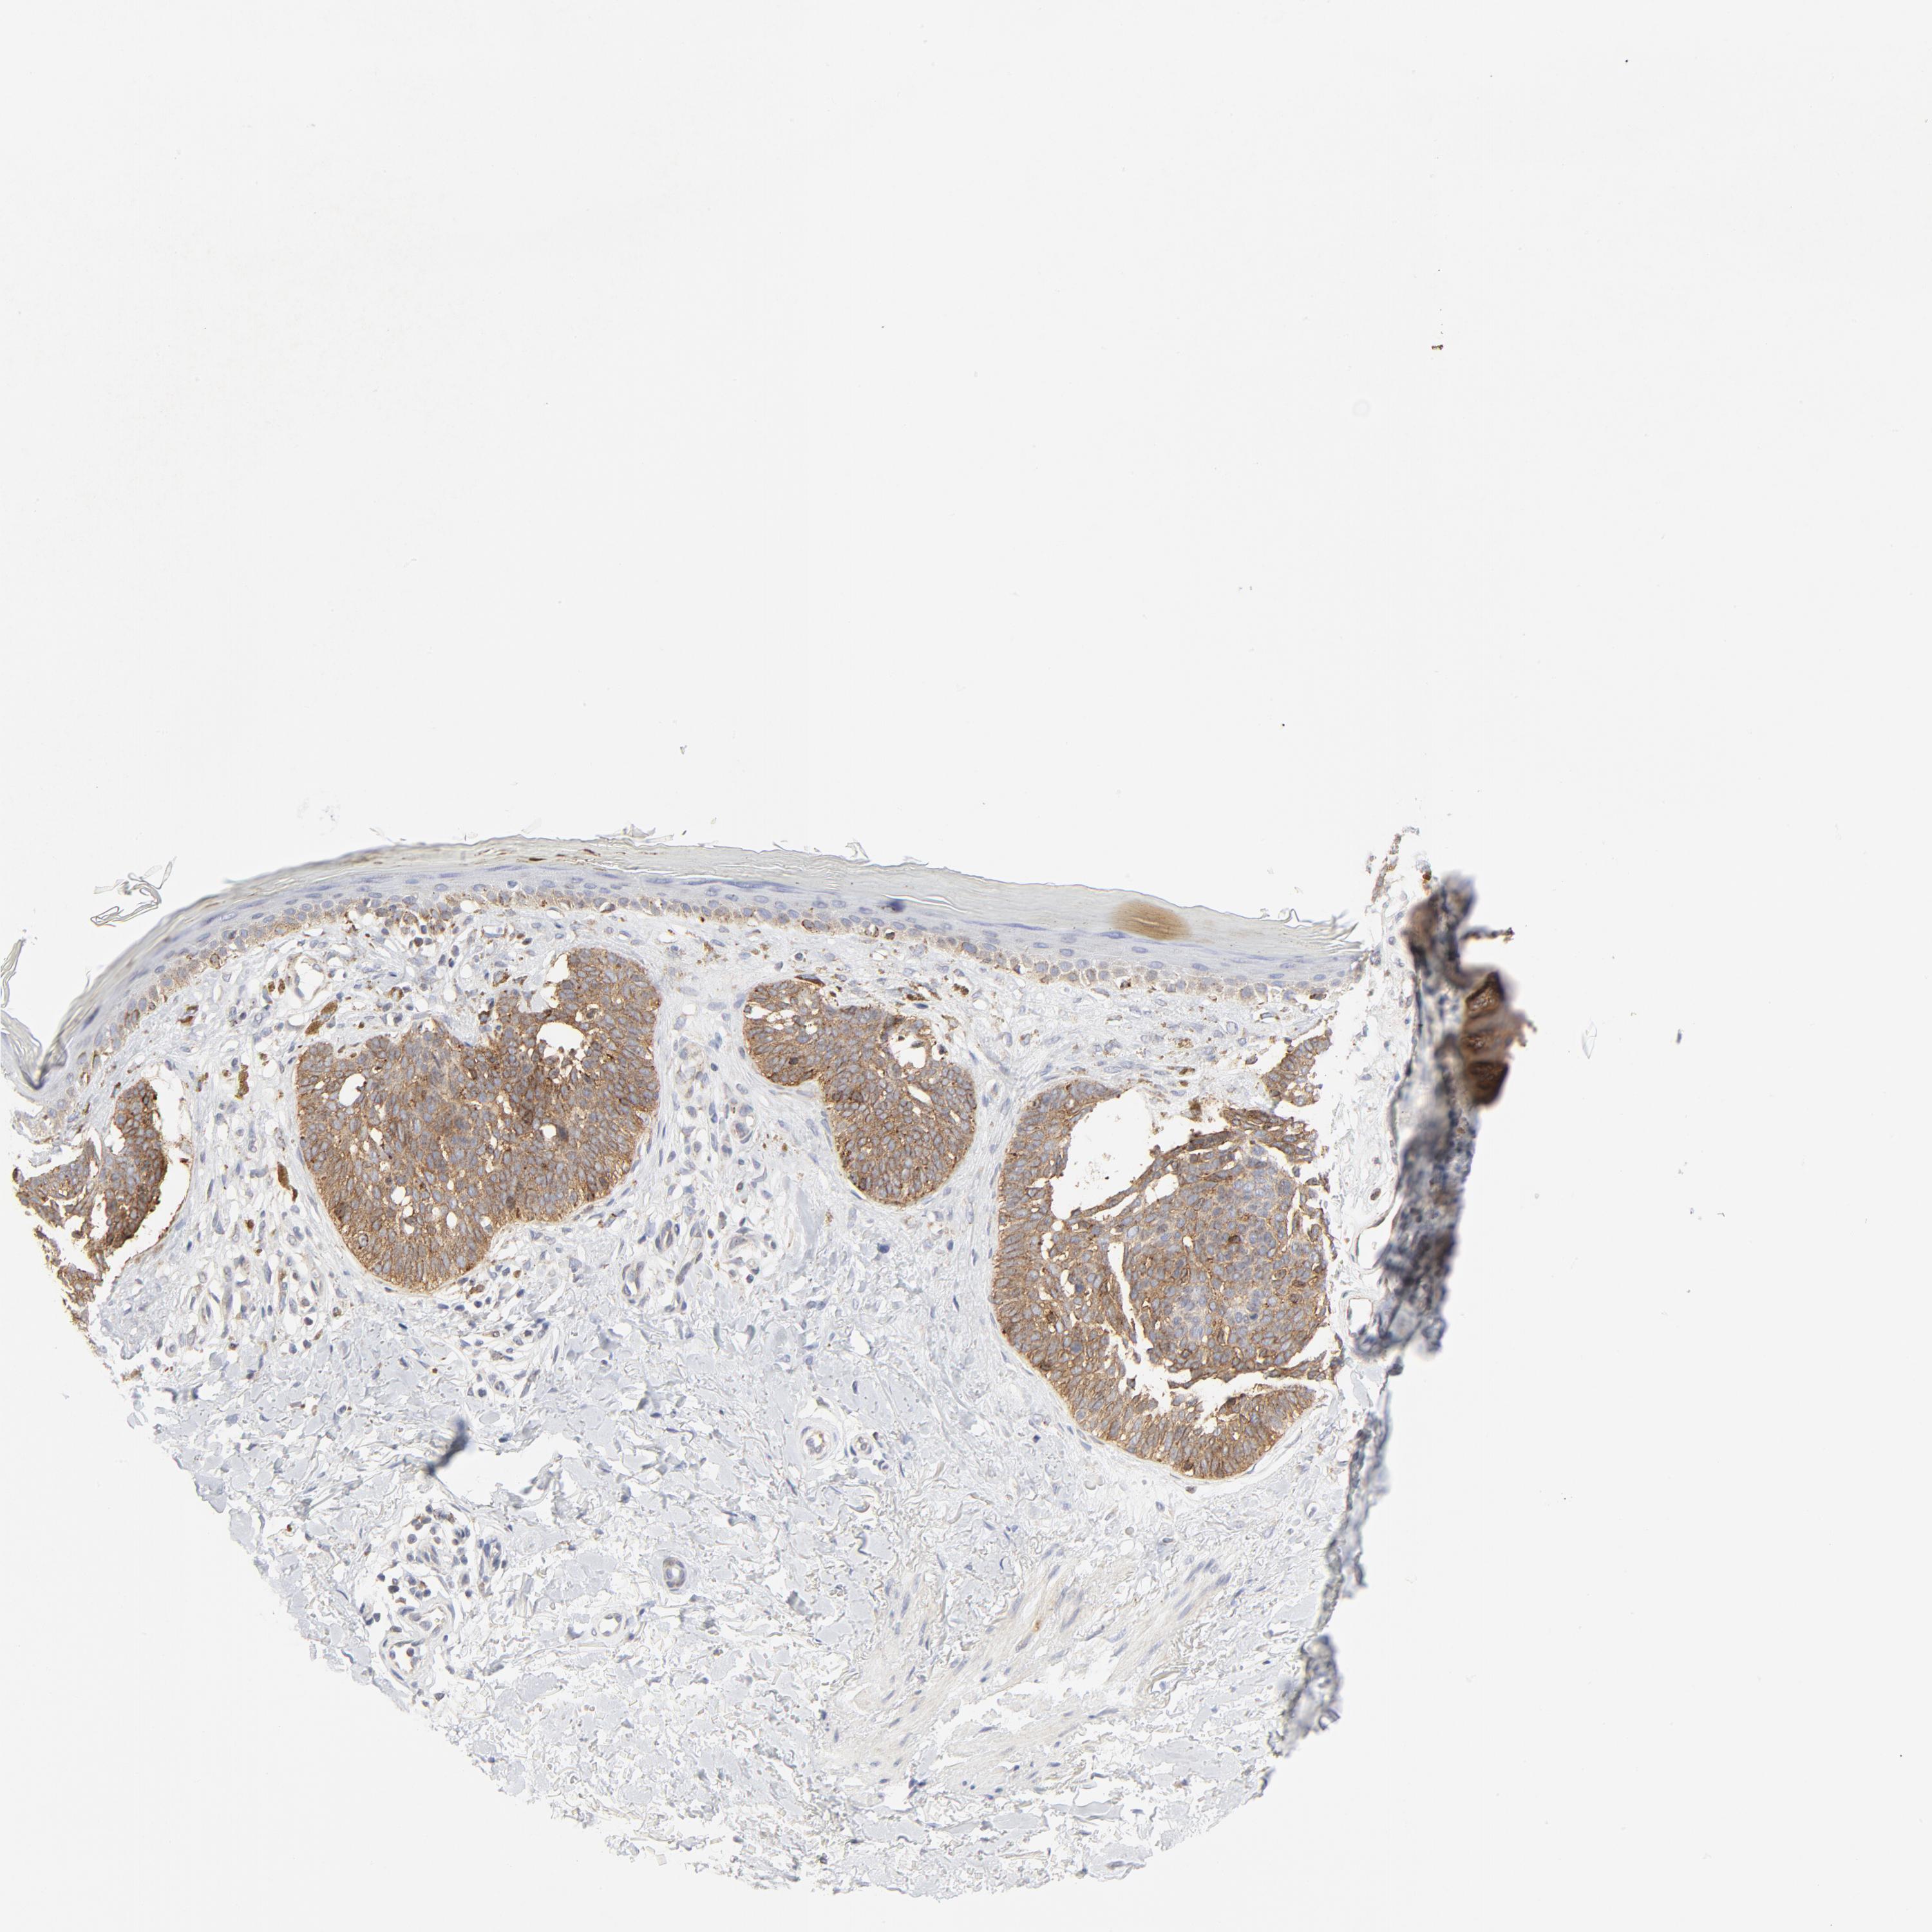

SKIN CANCER - Protein expressioni

A mouse-over function shows sample information and annotation data. Click on an image to view it in a full screen mode. Samples can be filtered based on level of antibody staining by selecting one or several of the following categories: high, medium, low and not detected. The assay and annotation is described here.

Each image is clickable and will lead to virtual microscopy that enables deeper exploration of all samples and also displays staining intensity scores, fraction scores and subcellular localization as well as patient and tissue information for each sample.

Antibody CAB004490

Squamous cell carcinoma, NOS

Squamous cell carcinoma, metastatic, NOS